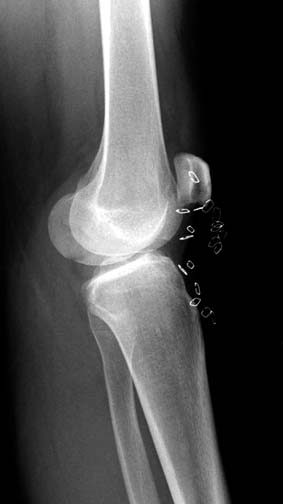

[Ortho] Нелеченный перелом Hoffa

Здесь представлены различные варианты фиксации перелома, а также снимки

комбинации перелома с повреждением хряща (12-19). Пластика хряща

OsseoFit и установка custom made plate.